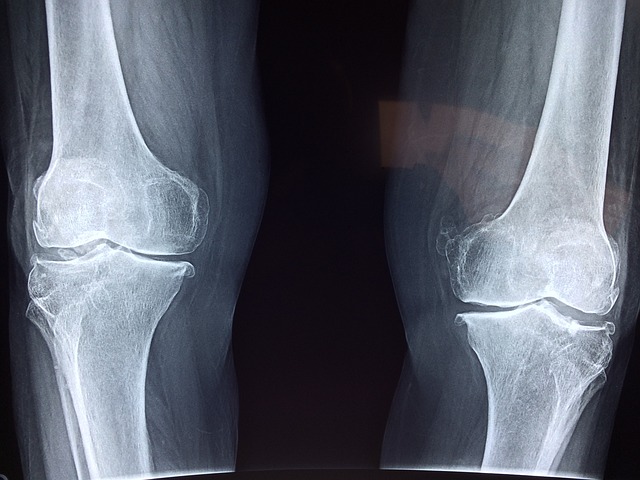

골다공증은 뼈의 밀도가 낮아지며 골절 위험이 증가하는 질환입니다. 특히, 고령화 사회에서는 이 문제가 더욱 중요하게 다루어져야 합니다. 🌍 오늘은 골다공증에 좋은 음식에 대해 자세히 알아보겠습니다.

골다공증은 뼈의 밀도가 감소해 골절 위험을 증가시키는 질환으로, 정기적인 관리와 예방이 필수적입니다. 난연기를 예방하기 위해서는 다음과 같은 전략을 세워야 합니다: